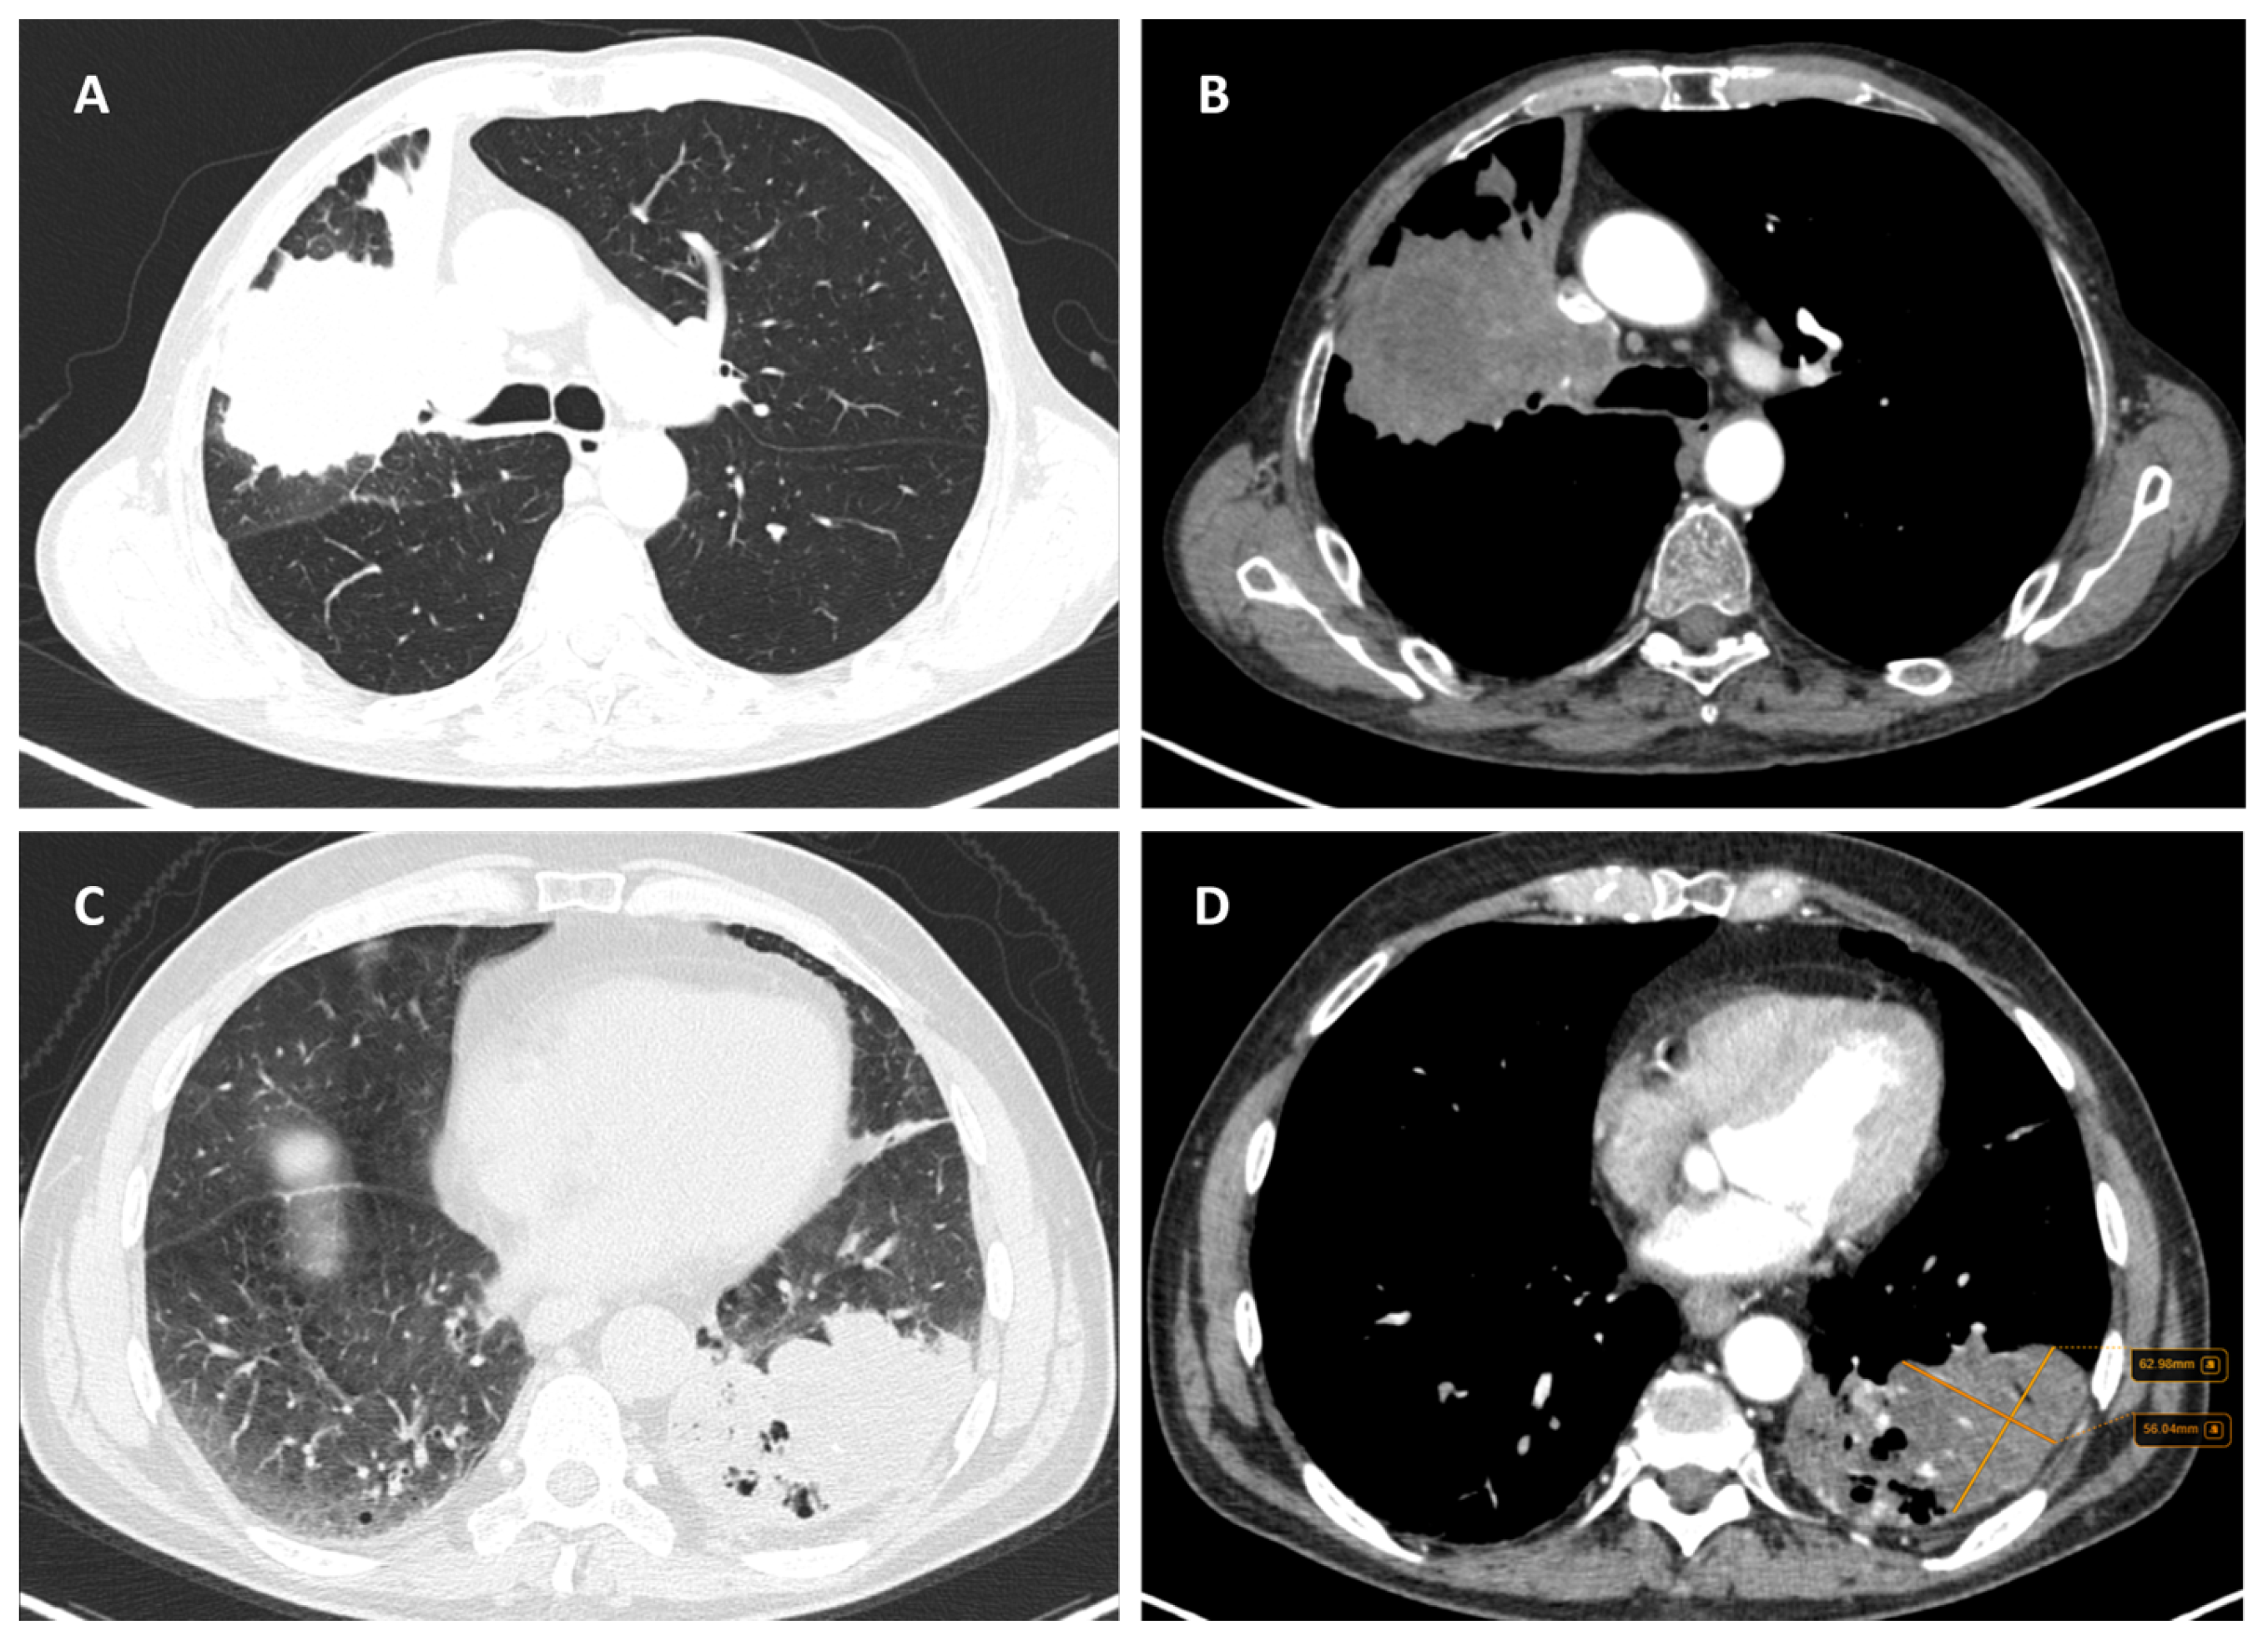

3.2.3. Tumoral Margins

3.2.4. Cavitation

3.2.5. Local Invasion